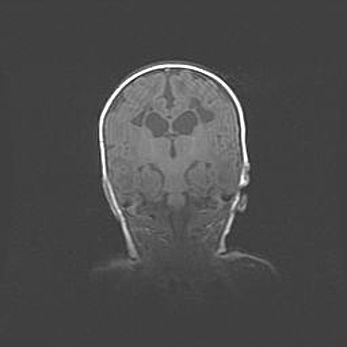

Лейкомаляция с кистозно-глиозной дегенерацией головного мозга.

Возраст: 2 месяца 25 дней

Вес: 6400 г

Окружность головы: 40 см

Срок гестации: 41 неделя

Лейкомаляцию относят к ишемически-гипоксическим повреждениям головного мозга, диагностируемым у новорожденных. При лейкомаляции в головном мозге обнаруживают очаги некроза, возникшие после тяжелой гипоксии и нарушения кровотока. В процессе морфогенеза очаги проходят три стадии: 1) развития некроза, 2) резорбции и 3) формирования глиозного рубца или кисты. Перивентрикулярная лейкомаляция (ПЛ) встречается примерно в 12% случаев среди новорожденных, обычно – у недоношенных детей, причем, частота ее зависит от массы, с которой младенец появился на свет. Наибольшее число малышей страдает лейкомаляцией, если масса при рождении 1500-2500 г.